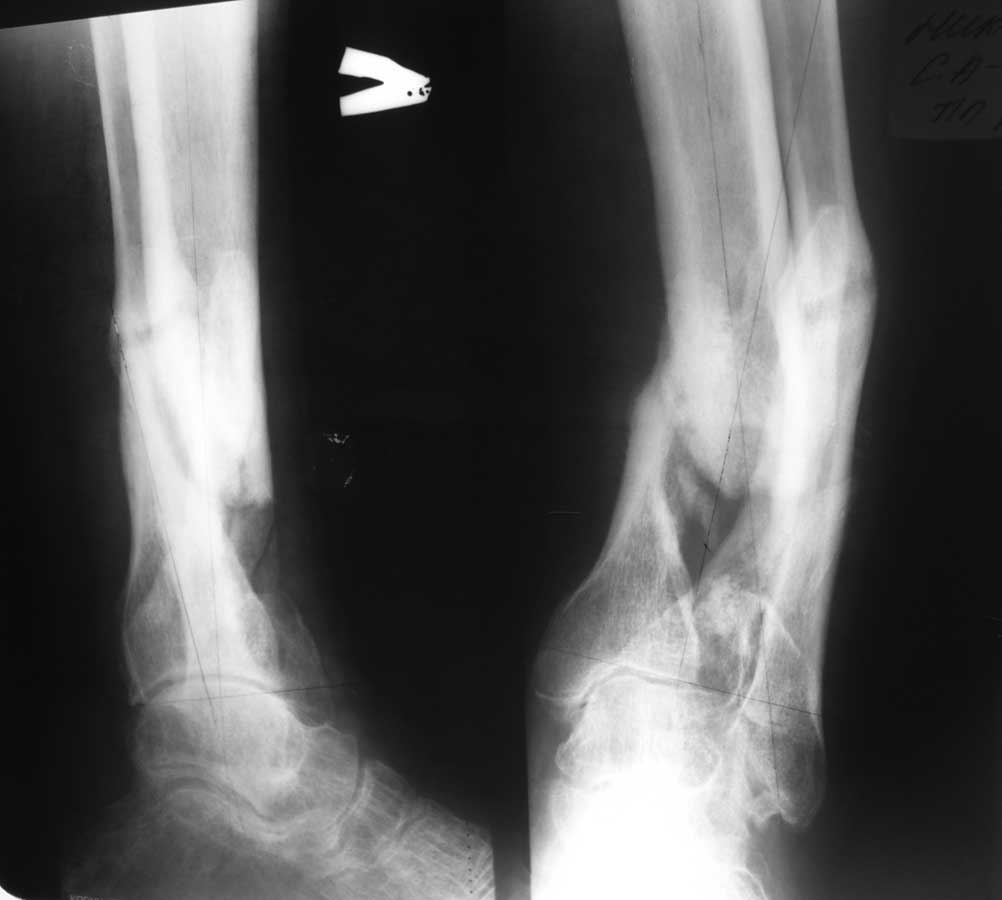

Re: Ложный сустав голени

Уважаемый Александр Николаевич! Вот фото рентгенограмм.